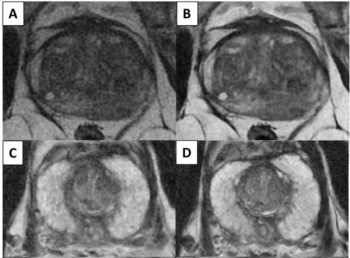

Developed by an extended prostate cancer working group of the European Society of Urogenital Radiology (ESUR), the updated PI-QUAL scoring system emphasizes a simplified scale of image parameters that applies to prostate MRI scans with and without intravenous contrast use.

Emphasizing restriction spectrum imaging (RSI), the recently launched prostate MRI software OnQ Prostate may enhance PI-RADS assessments and workflow efficiency.